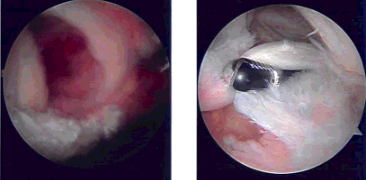

The shaver was entered from an anterosuperior portal and subacromial decompression and bursectomy was performed. An accessory lateral portal was made. The scope was entered from the lateral portal and the shaver was entered from the posterior to complete the debridement.

A thermal ablation wand was used to prepare for acromioplasty. A 6.0 burr was used to perform the acromioplasty. After acromioplasty was performed, the rotator cuff tear was debrided and demarcated. The head of the humerus was tapped with the use of shaver and burr for the repair of the rotator cuff.

The biceps could be seen. Healicoil triple-loaded was inserted after tapping into the head of the humerus. All six tails of the Healicoil were passed through the rotator cuff tear from anterior to posterior avoiding the biceps. The sutures were tied onto each other with knots. Good repair was achieved.

Pictures were taken. A distal clavicle excision was planned, finding an osteophyte there. A distal clavicle excision was done from the posterior portal following the anterior portal. About a centimeter of distal clavicle was excised. Final pictures were taken and saved.